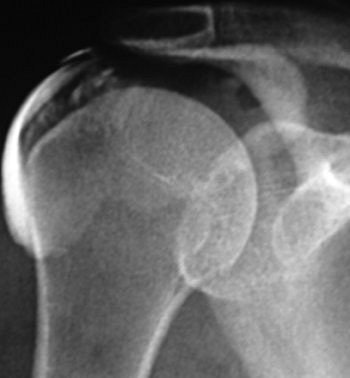

| A 46-year-old woman with inflammatory changes in acromioclavicular joint with osteophyte formation, secondary impingement, and bursitis (grade 2). Symptom duration was four months, and patient reported complete resolution of symptoms after six months of follow-up. Subacromial bursogram shows inflammatory changes in acromioclavicular joint. |

The authors found that patients of all ages (mean age of 48.6) benefited from treatment. Of the 40 who reported complete resolution, 40% had duration of symptoms of less than three months. In terms of MRI grade, in those patients with partial resolution or no change, the MRI grade increased. They noted that the "mean duration of symptoms was significantly shorter among patients with complete resolution than those without" (American Journal of Roentgenology, November 2007, Vol. 189: 1179-1184).

![]() |

| Same patient as above. Symptom duration was four months, and patient reported complete resolution of symptoms after six months of follow-up. Coronal oblique STIR MR image (TR/TE, 2,000/20; inversion time, 160 msec; echo-train length, 8) shows changes in acromioclavicular joint (open arrow) with osteophyte formation (closed arrow). Hambly N, Fitzpatrick P, MacMahon P, and Eustace SW, "Rotator Cuff Impingement: Correlation Between Findings on MRI and Outcome After Fluoroscopically Guided Subacromial Bursography and Steroid Injection" (AJR 2007; 189:1179-1184). |

Overall, the authors found that better outcome was associated with shorter duration of symptoms, minor-grade MRI findings (1 and 2), and younger patient age. Given that 83% of the patients reported some form of relief after steroid injection, the authors concluded that the procedure has value for the short-term management of subacromial bursitis. A lack of response to treatment should prompt a search for an alternative cause, such as nerve root impingement, they suggested.